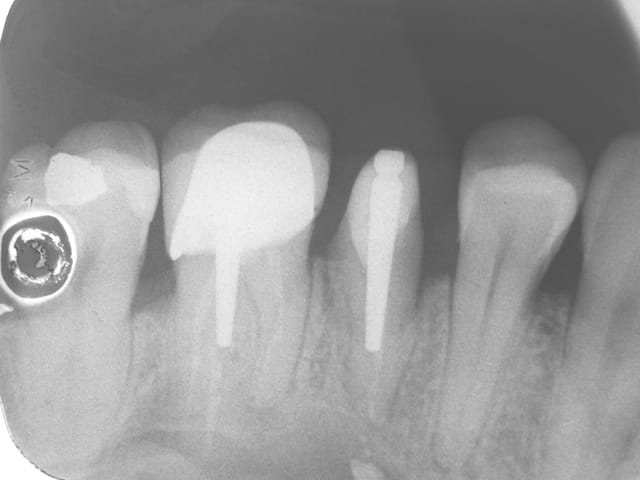

05/08/2014 à 11h37

ci joint la radio de controle du coup du loukoum :soit 1 an apres extraction reimplantation

http://www.eugenol.com/sujets/406035-1ere-fois-que-ca-m-arrive?page=32